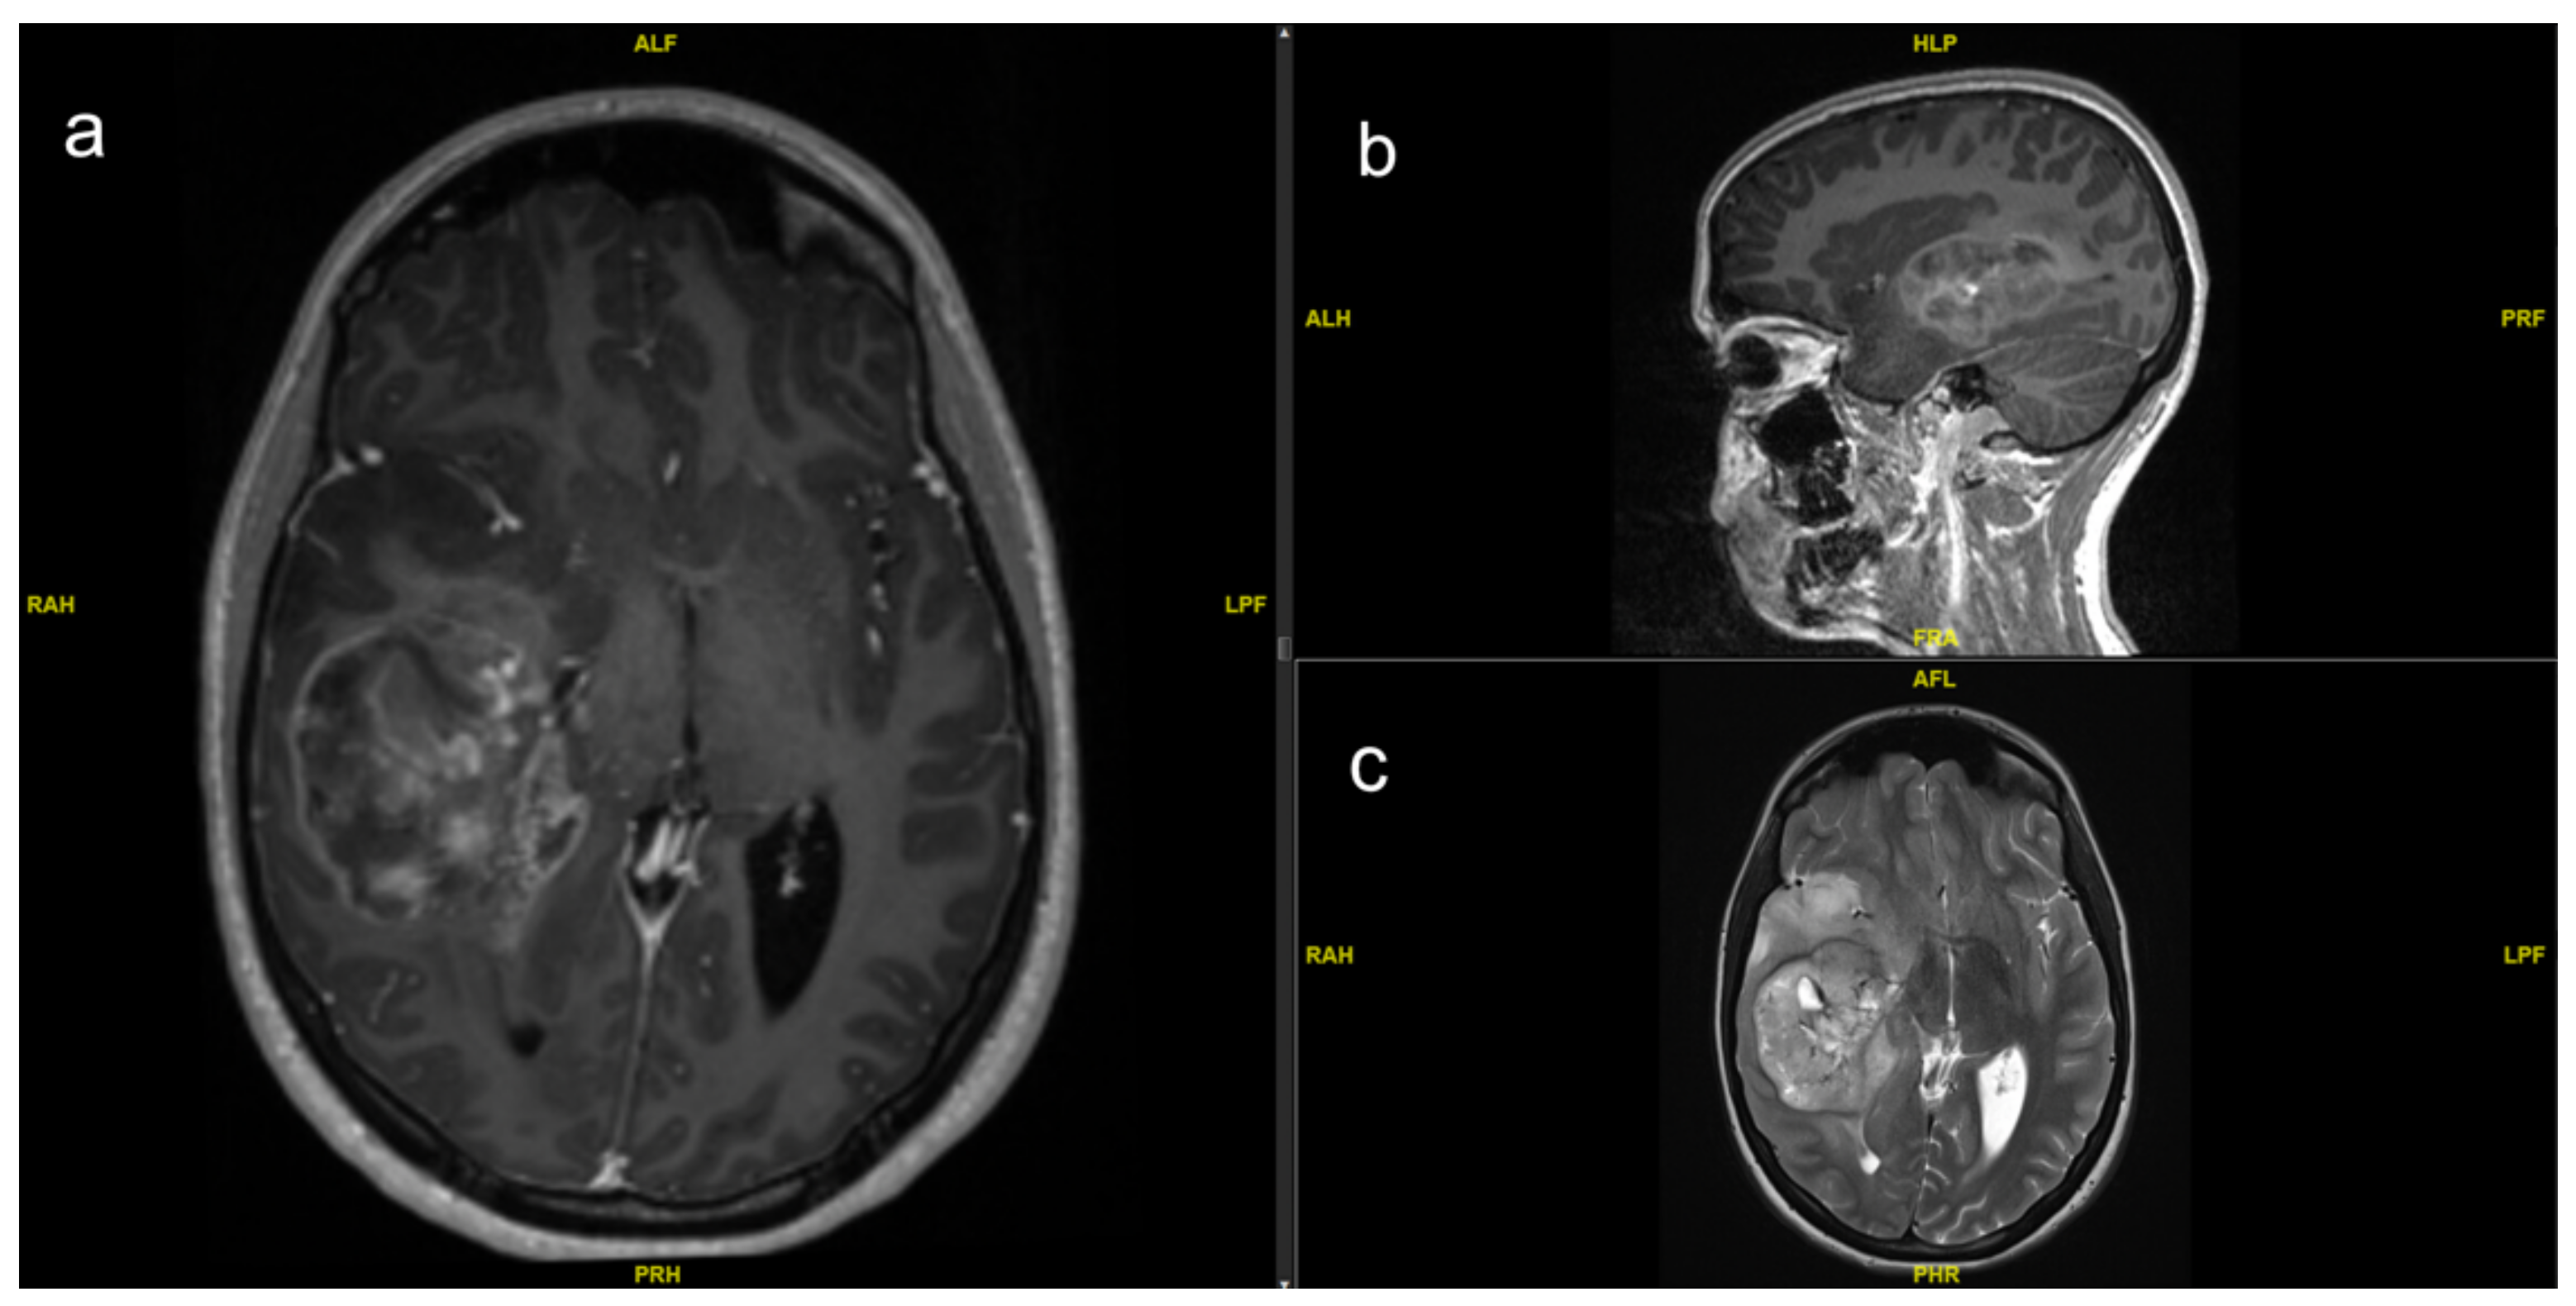

- Junior, A.G.; Abreu, N.M.P.; Leal, M.V.B.; de Aquino, H.L.A.; Rodrigues, J.P.C.; Malveira, C.B.; Silva, Y.P.; Coimbra, P.P.A. A Case Report of a Rare Pediatric Brain Tumor: Congenital Glioblastoma. Cureus 2022, 14, 3229. [Google Scholar] [CrossRef] [PubMed]